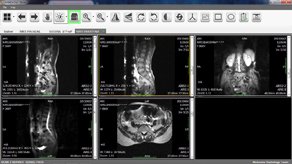

Brand new Workstation for all your radiology needs.

Intelligence lenses on screen to read all images.

World class Kins PACS system with affordable cost.

Art of imaging with proven idea to increase care on patient and revenue.